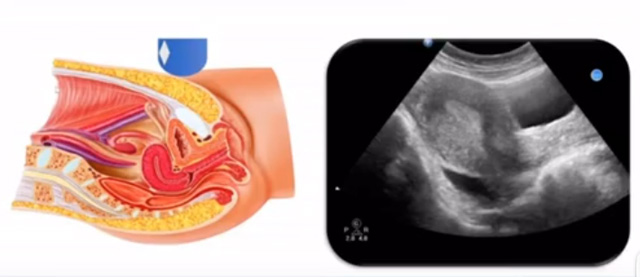

女性生殖系統(tǒng)包括內、外生殖器官及其相關組織以及鄰近器官,其中內生殖器是我們超聲檢查的主要對象。那么內生殖器包括陰道、子宮還有輸卵管及卵巢。輸卵管及卵巢稱為子宮附件。子宮是倒置梨形,但是它是空腔厚壁肌性器官。它的正常值在育齡婦女。超聲探頭放在貼近腹壁盆腔上面位置,來看這個子宮在超聲上面的表現(xiàn)。從輪廓上來講,和示意圖是一樣的。這就是在超聲上面顯示的一個子宮的圖片。子宮在不同的時期與子宮頸的比例。成年婦女指的是育齡婦女為2:1子宮體是比較大的,嬰兒期為1:2說明宮頸比較大,絕經期1:1。所以我們在看到子宮圖時候可以根據(jù)宮體宮頸比例大致可以推測屬于哪個時期的婦女。另外還可以根據(jù)比例大小來推斷是一個正常子宮還是異常子宮。

子宮從外到內,漿膜層、肌層、粘膜層。宮體部宮頸為梭形結構。宮腔為上寬下窄的三角形,連接為峽部。子宮有什么功能呢?月經血產生跟排出通道,精子運行通道受精作用。囊胚著床及胎兒發(fā)育、生長的場所。分娩時產生宮縮使胎兒、胎盤娩出。未孕的子宮是很小的,已孕子宮就非常大,平均胎兒都有6斤重。所以這個后壁就體現(xiàn)出來。輸卵管由子宮角部向外延伸,為一對細長而彎曲的管道,呈管狀中空結構,大概長度是8-14厘米,粗1-4毫米,它的下方為卵巢和闊韌帶。間質部是厚一點的,峽部是比較窄的地方,壺腹部,漏斗部。正常情況下,輸卵管在普通超聲DR難以顯示。